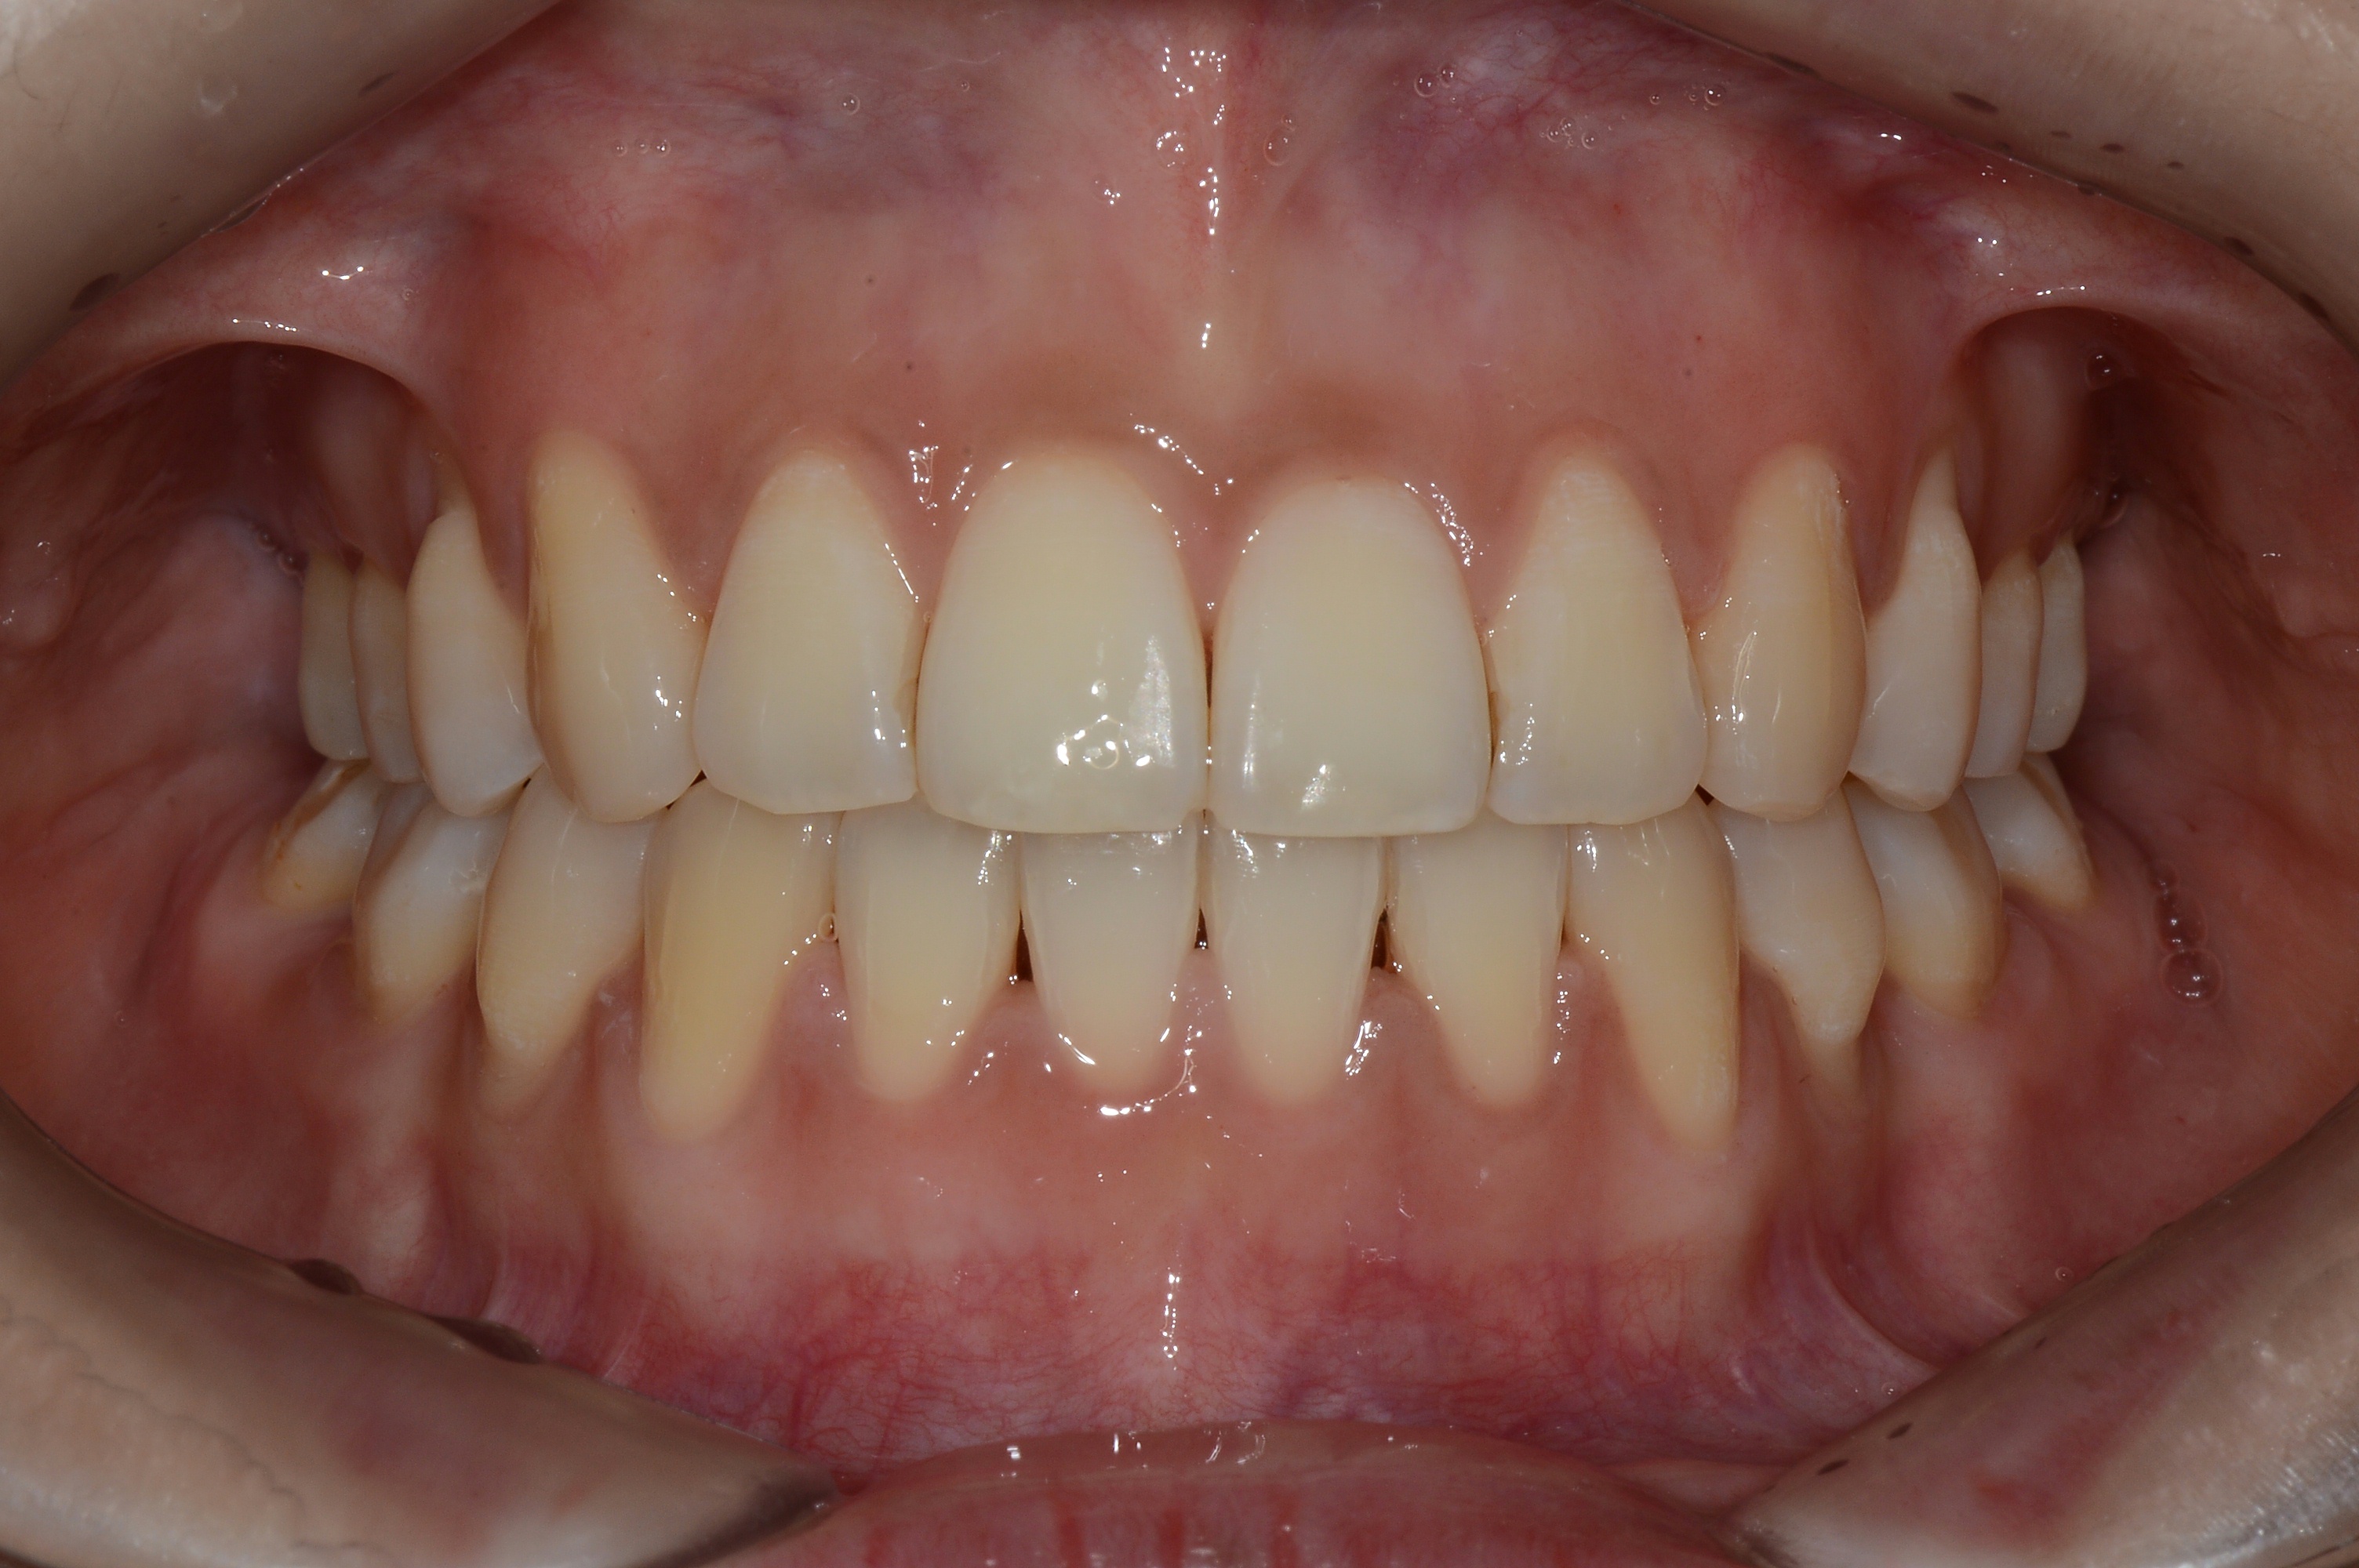

치료 후 사진입니다.